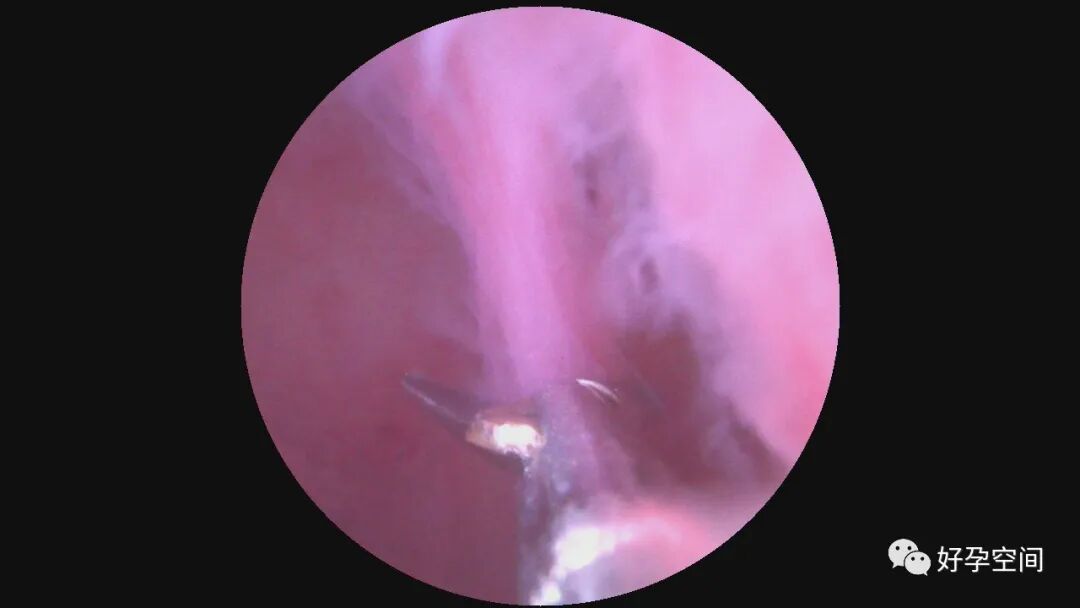

病例1:61岁,G2P1,剖宫产1次,原发性高血压。安环28年,绝经3年。病人肥胖,身高156cm,体重85kg。阴道深,一次性扩阴器勉强暴露宫颈,宫颈萎缩,宫颈钳很难夹持住,反复松脱,置入一次性宫腔镜见节育环坎顿,异物钳艰难取出节育环,偶然见宫腔下段后壁息肉,约1.5cm*1.0cm*0.8cm,异物钳从根部摘除息肉。

病例2:51岁,G2P1,顺产1次。安环29年,绝经1年,发现宫颈息肉1月。一次性宫腔镜见T型环嵌顿于宫腔,铜环套破碎,异物钳取出。宫颈管息肉约2.5cm*1.5cm*1.0cm,息肉根部位于宫颈管下段前壁,单级电针切除息肉。